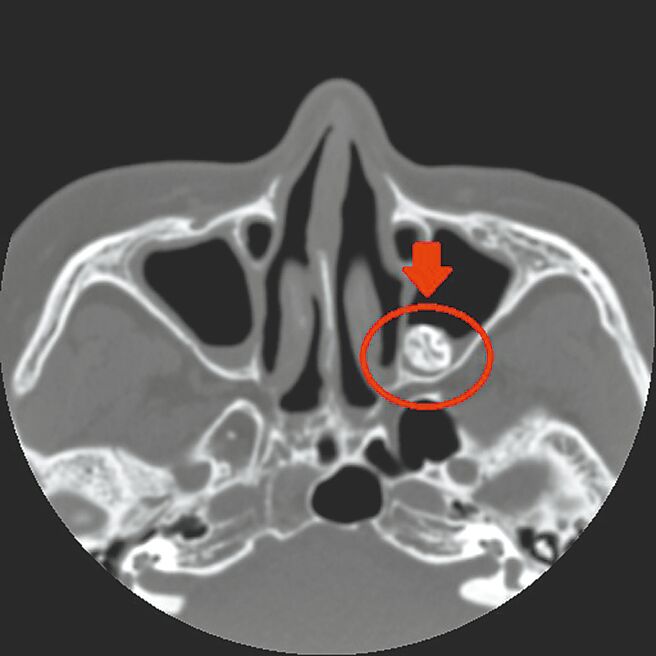

经核磁共振检查,在妇人的左上颚窦位置处,发现1颗外型及密度都疑似「牙齿」的不明物体,研判是「异生齿」,医师建议藉由外科手术取出改善,妇人术后隔天即出院返家。

田辉勣指出,这颗鼻窦异生齿位置十分特别,经沟通后,患者同意採用「自然孔」(鼻腔)执行手术,过程中透过磁导航3D立体定位系统,快速找到异生齿位置并取出,前后仅耗时30分钟,取出的异生齿约2公分大。